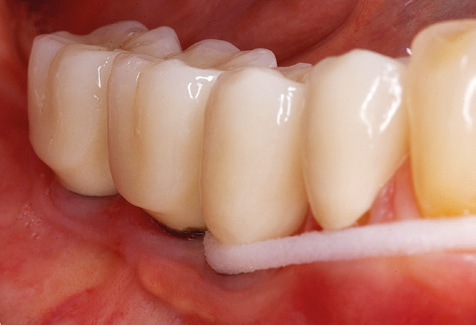

A 52-year-old patient presented in our clinic for the first time in 2004 following tooth loss in the third quadrant, expressing a desire for a new prosthetic restoration. Periodontal and radiological diagnostics revealed the need for extensive periodontological treatment. In addition, teeth 48, 28 and 27 were attributed a very poor prognosis and were subsequently extracted (Fig. 1). Following the successfully completed, systematic periodontological treatment, a fixed dental implant was inserted with the introduction of five implants in tooth regions 35, 36, 37, 46 and 47. Prosthetic treatment of the natural teeth was effected with veneered zirconium dioxide ceramic crowns; the implants were composed of two-piece, individual zirconium dioxide abutments and similarly veneered crowns made of a zirconium dioxide ceramic (Cercon base colored, Dentsply Sirona Lab). Definitive insertion of the prosthetic restoration occurred in 2005.

Due to the presence of periodontal disease, SPT was performed every three months in the first years following the insertion. The patient demonstrated a high degree of motivation and good compliance. The pocket depths recorded annually revealed a stable periodontal situation with a BOP index of below five per cent. On the basis of the stable periodontal situation and good cooperation on the patient’s part, the recall interval was extended to every six months as of the sixth year of the prosthetic function phase. Following the change in the recall interval, the respective annual documentation of the periodontal status continued to reveal a stable periodontal situation with no increase in the pocket depths and a BOP index below five per cent (Fig. 2a and b).

The ten-year check-up revealed no indications of advancing clinical attachment loss or peri-implant bone substance loss (Fig. 3).

The patient continues to visit the clinic every six months for SIT. In the following, the patient is taken as an example for demonstrating the individual working steps in a structured SPT session as it has been performed with barely any modifications over the last 12 years. Of course, some new materials and devices have been integrated into the concept over the years. This clinical case report presents the current material and device concept.